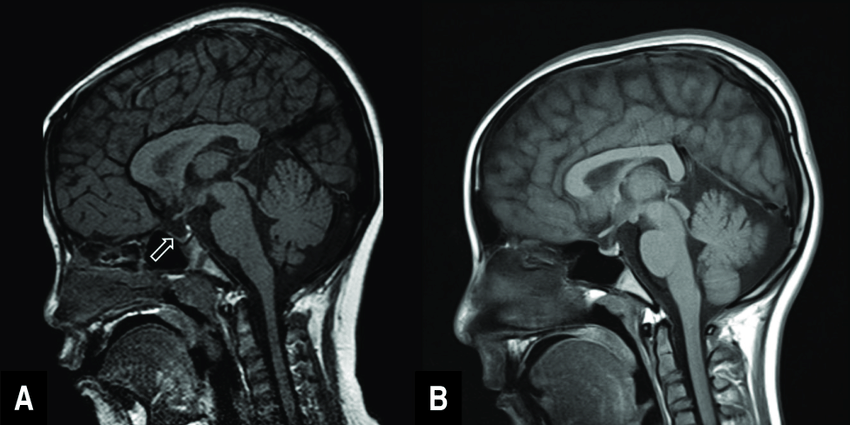

PRESENTER Ruben Onsu, 40, beberapa waktu lalu pernah mengungkapkan ia menderita penyakit langka berupa empty sella syndrome (ESS). Wajahnya terlihat pucat dan tubuhnya tampak kurus. Bahkan, ia sempat dirawat di sebuah rumah sakit. Ruben juga mendapatkan transfusi darah. Hal yang serupa terjadi tahun lalu yang bahkan menyebabkan ia harus masuk ICU.

"ESS merupakan keadaan yang langka ditemukan. Kebanyakan ESS tidak bergejala sehingga dideteksi tanpa sengaja saat pasien melakukan pemeriksaan kepala," kata Dokter Spesialis Bedah Saraf Rumah Sakit Siloam Kebon Jeruk dr Petra OP Wahjoepramono SpBS saat dihubungi, Selasa (9/5).

ESS merupakan penyakit yang menyerang otak bagian sella turcica atau ruang dasar otak tempat kelenjar pituitari yang sebenarnya berfungsi untuk menghasilkan hormon pada kesehatan.

Terdapat dua tipe ESS, yakni primer dan sekunder. Pada ESS primer, kelenjar pituitari biasanya berbentuk pipih. ESS jenis itu lebih sering terjadi pada wanita yang mengalami obesitas dan memiliki tekanan darah tinggi. Itu juga diduga menjadi penyebab penumpukan cairan di otak.

Sementara itu, pada ESS sekunder kelenjar pituitari mungkin mengecil karena perubahan genetik (mutasi), cedera, terapi radiasi, atau pembedahan.

Petra menjelaskan jika pasien tidak pernah menjalani operasi kepala, radiasi, atau cedera kepala yang berat, ESS biasanya disebabkan pembentukan lapisan otak yang tidak sempurna di daerah sella. Pemeriksaan fisik yang diperlukan untuk diagnosis ESS ialah CT scan dan MRI. "ESS kebanyakan ditemukan tanpa sengaja," jelasnya.